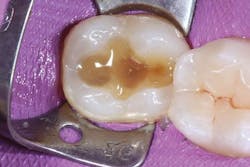

After adhesive treatment, Tetric EvoFlow Bulk Fill (IVA shade, Ivoclar Vivadent) was injected on the pulpal floor of the cavity in an increment of 4 mm, leaving the thickness for packable resin composite approximately 1.2 mm from the cavosurface margin to allow for final sculpture of the occlusal surface per the manufacturer’s recommendation. After light polymerization, the dentin-like opacity of Tetric EvoFlow Bulk Fill was observed, which masked the dark stump shade and improved esthetics. (figures 4 and 5).